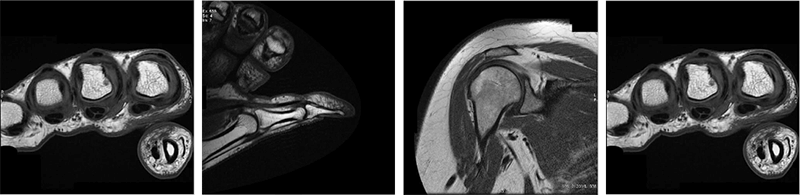

Here some examples of images made with the spin-echo sequence on various anatomical structures. As we have already discussed, this sequence is generally reserved for T1 weighting due to its acquisition time.

- Image 1 – here we have an axial T1 SE of the brain. Recall from earlier modules, the CSF is dark because of the long T1 relaxation time, and the fat around the skull is bright because it has a short T1 time

- Image 2 – The second image is a T1 SE of the thumb in the sagittal plane. Note the dark appearance of the tendon. Again, we know that means it has a long T1 time

- Image 3 – This image is a T1 SE of the shoulder in the coronal plane. We can easily differentiate between the fat and the muscle because of the different T1 relaxation times. This is what we refer to as tissue contrast

- Image 4 – this last image we have a T1 SE Coronal sequence of the hand

T1 weighted sequences are most often used for anatomical structures and anatomy. We do not get much information about a pathology from a T1 sequence.